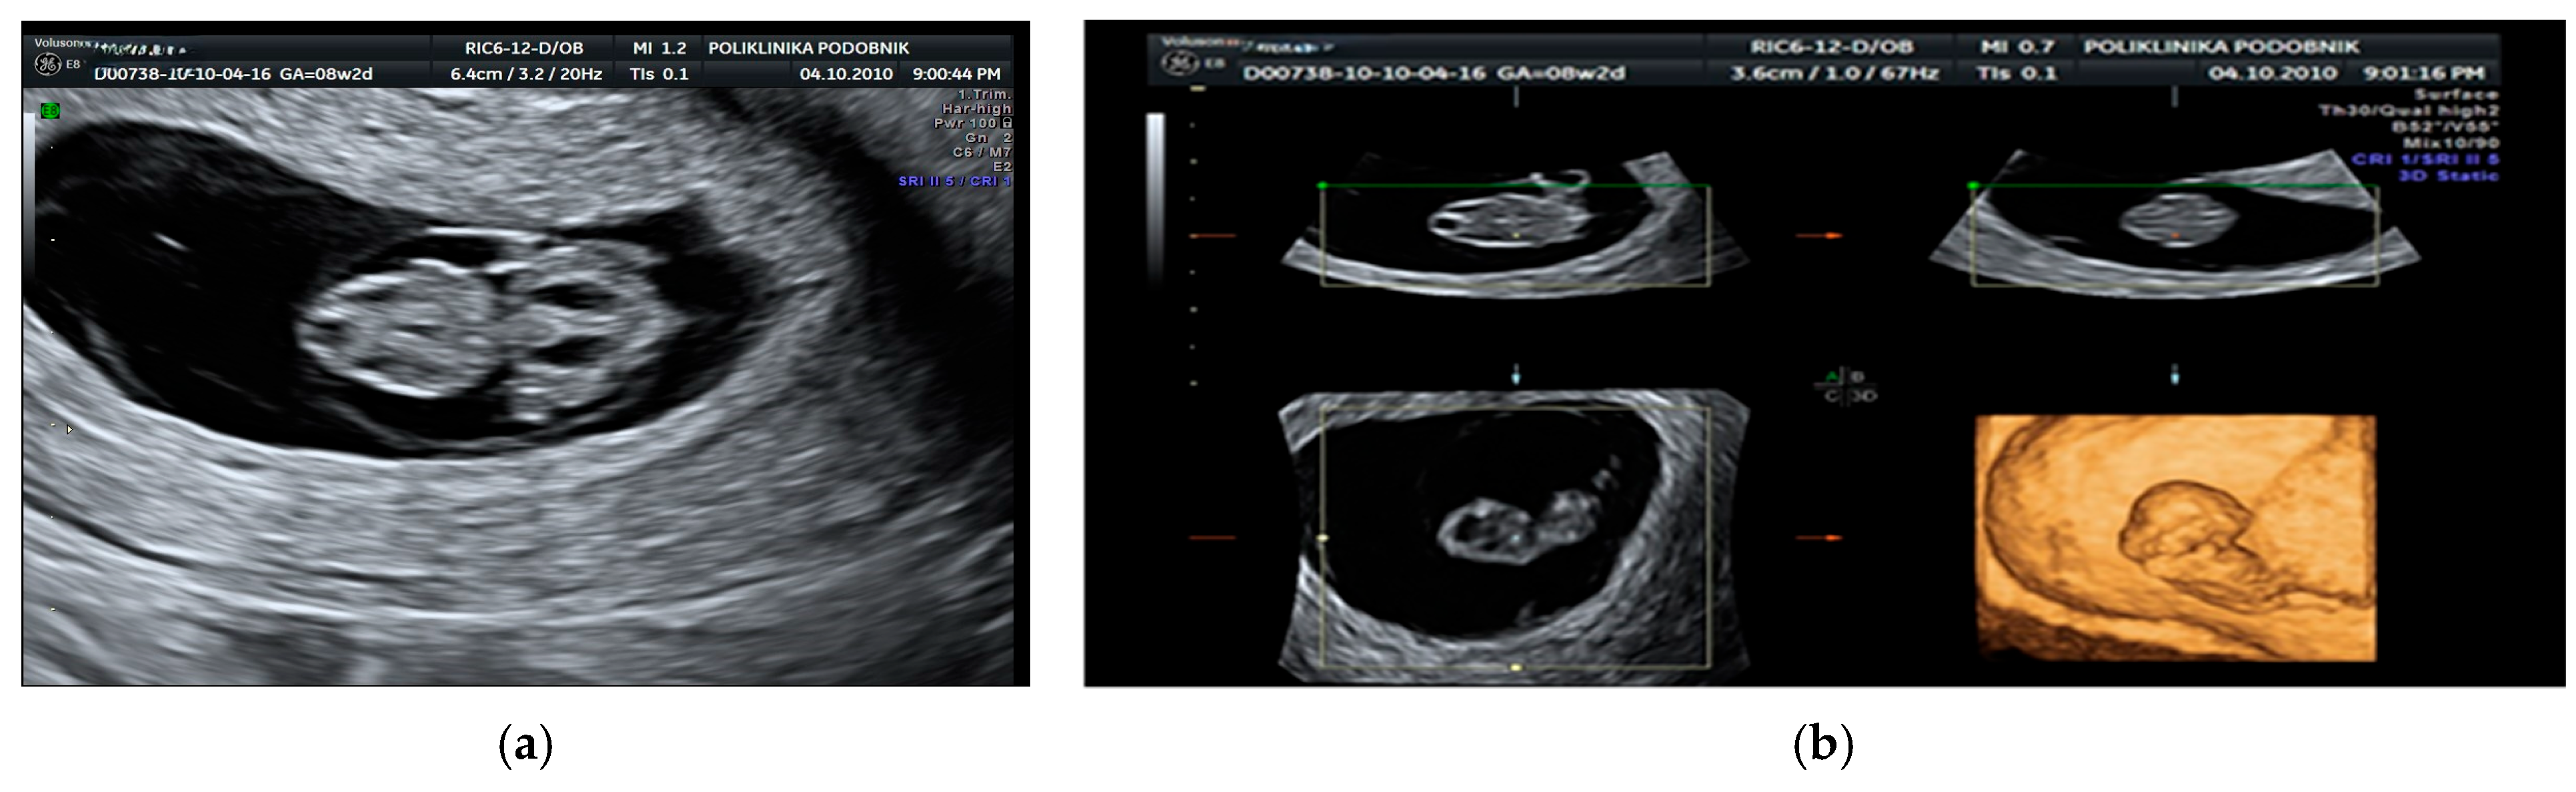

- Podobnik, M.; Singer, Z.; Podobnik-Šarkanji, S.; Bulić, M. First trimester diagnosis of cystic hygromata using transvaginal ultrasound and cytogenetic evaluation. J. Perinat. Med. 1995, 2, 283–291. [Google Scholar] [CrossRef] [PubMed]